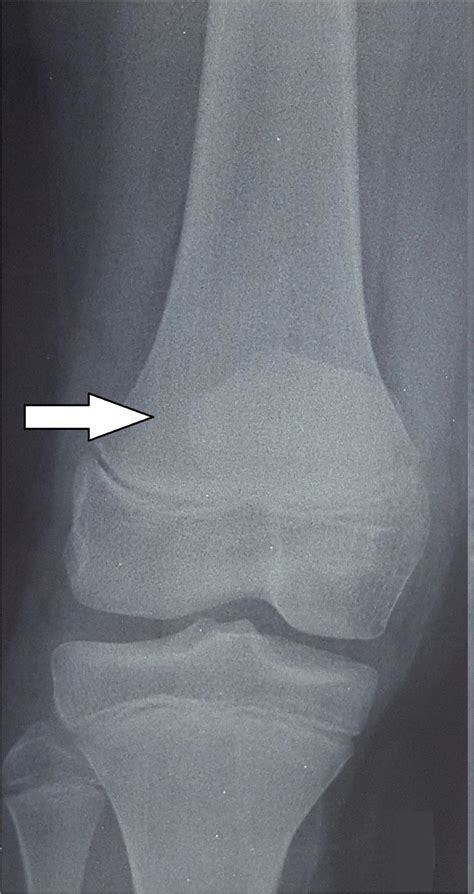

To confirm the diagnosis, medical professionals typically utilize imaging studies. X-rays are the gold standard for visualizing the displaced bone fragment and determining the severity of the fracture. In more complex or comminuted cases, an MRI may be ordered to assess the condition of the surrounding soft tissues, including the patellar tendon and menisci.

• tibial tuberosity fracture radiology